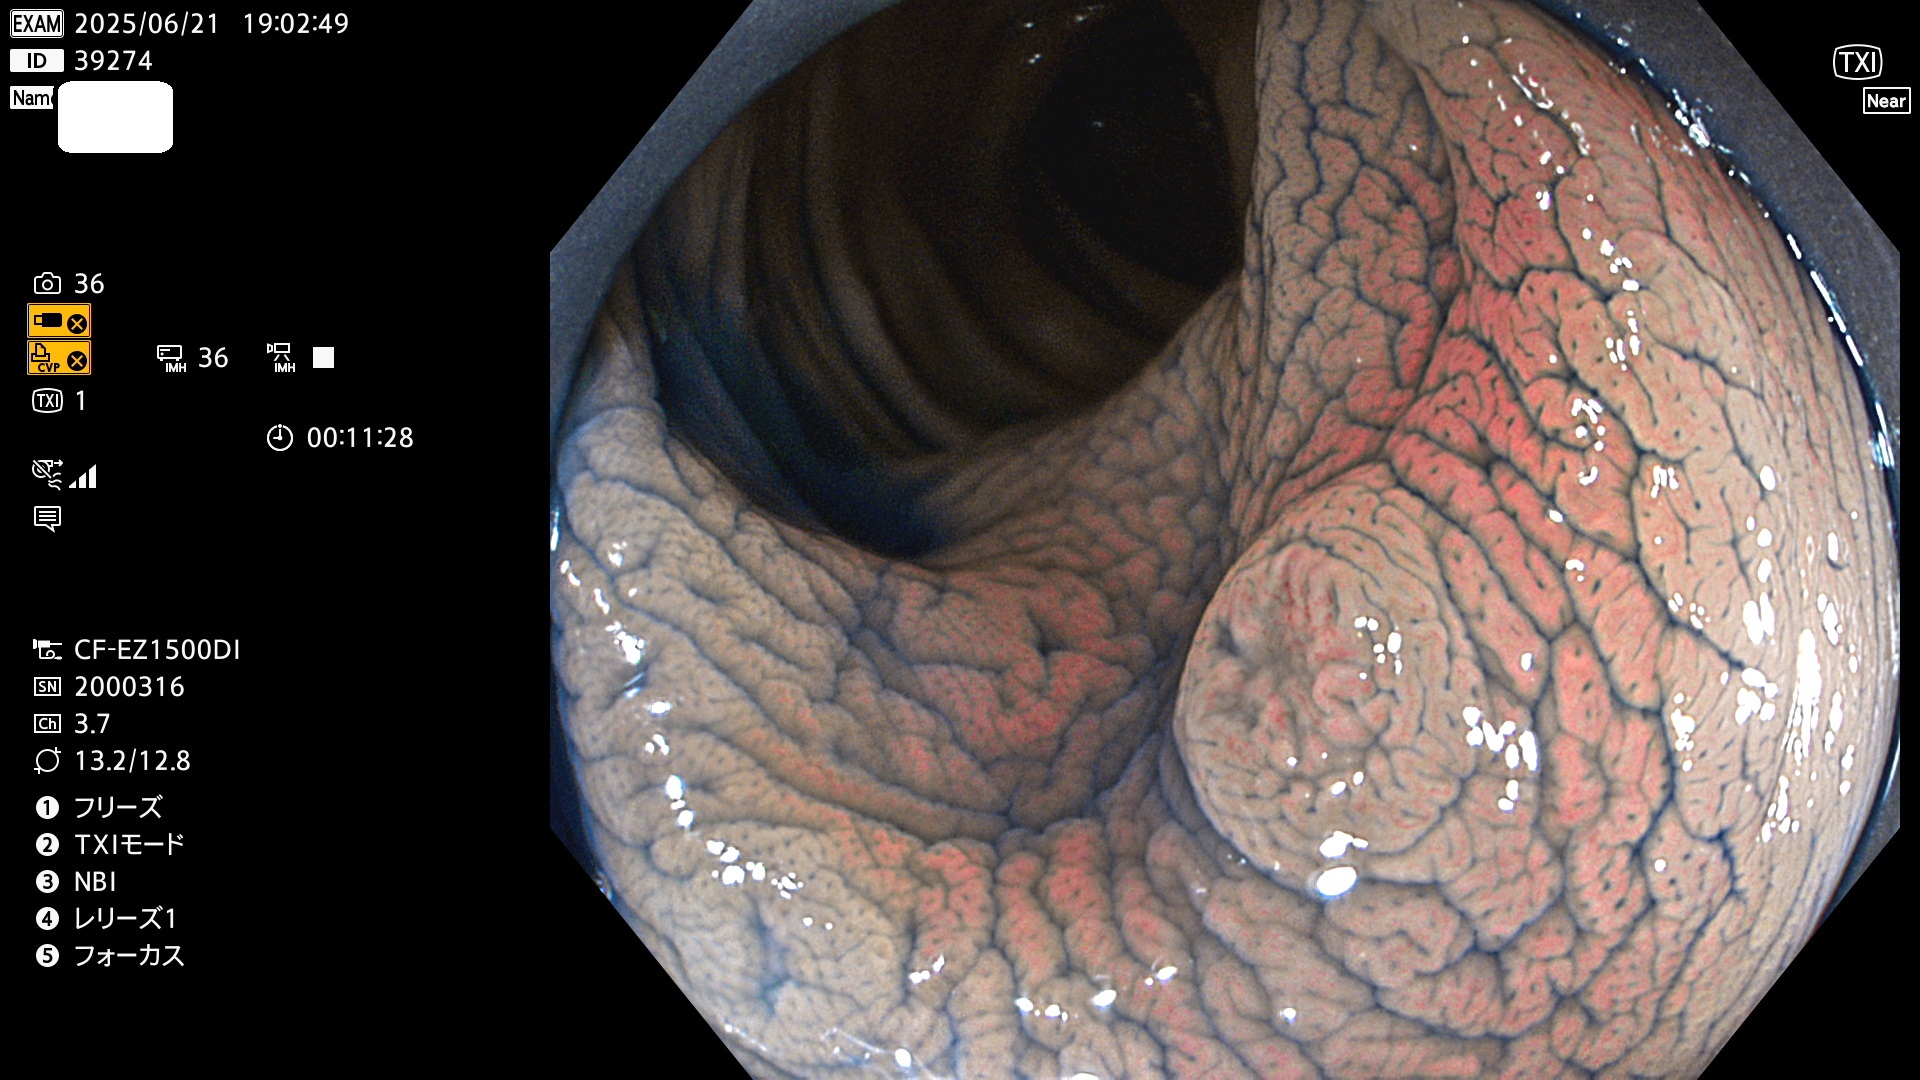

完全に平坦な物をUb、陥凹している物をUcと呼びます。Ubは認識が困難で、Ucはびらん(炎症)と紛らわしいために見落とされやすく、「内視鏡後・大腸癌」の原因になります。

抽出の対象期間 2025年6月19日〜6月22日の4日間(48件の検査)10個 (10/48=20%)